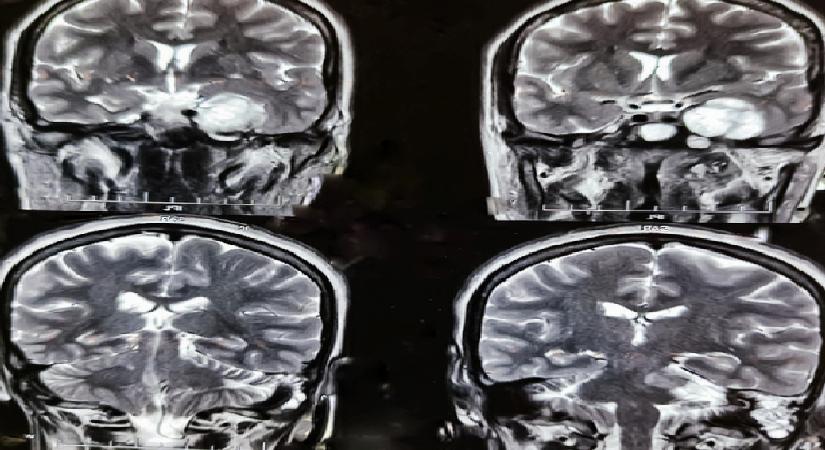

Beyin cerrahisinde artık “daha çok kesi” değil, “daha akıllı cerrahi” ön planda oluyor. Hibrit ameliyathanelerde kullanılan ileri teknolojiler sayesinde operasyonlar çok daha inançlı hale geldi.

Beyin cerrahisinde kullanılan çağdaş teknolojiler, operasyonların muvaffakiyetini ve güvenliğini en üst düzeye taşıyor.

Bu kapsamda nöronavigasyon teknolojisi cerraha tümöre ulaşması için en kısa ve inançlı rotayı belirleyen dijital bir yol haritası sunarken; işlevsel MR ve traktografi sistemleri beynin konuşma, hareket ve görme üzere hayati merkezlerini haritalandırarak bu kritik bölgelerin korunmasına yardımcı oluyor.

Öte yandan, cerrahi müdahalenin mümkün olmadığı yahut kuşkulu görülen lezyonlarda devreye giren stereotaktik biyopsi ise yüzde 95 üzere yüksek bir doğruluk oranıyla emniyetli teşhis konulmasına imkan sağlıyor.